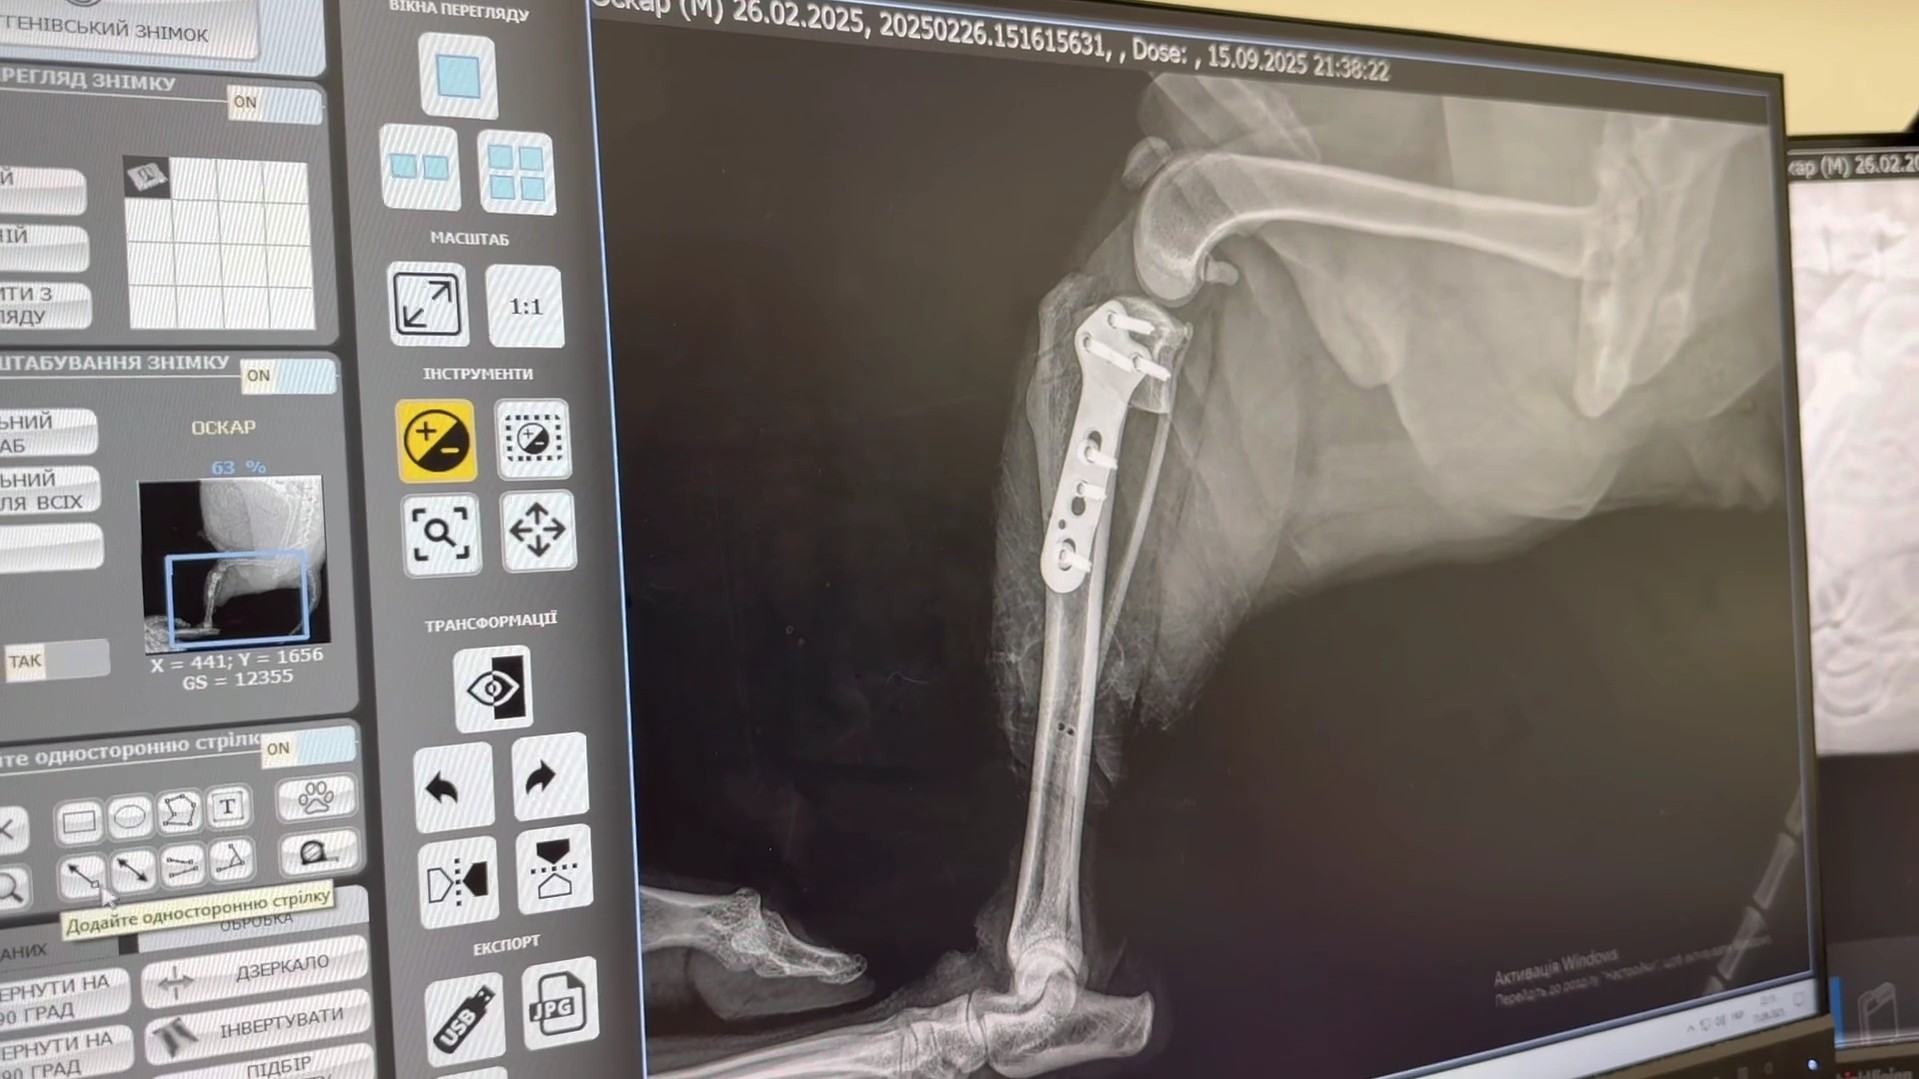

Topic No. 1 — TTA TECHNIQUE

Topic No. 2 — TPLO TECHNIQUE